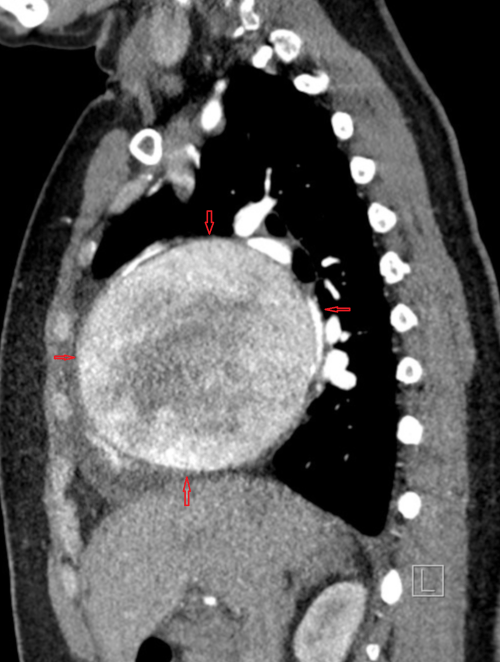

A 38-year-old women,with episodic chest discomfort, mild dyspnea, and occasional non-productive cough. She was investigated in a non-emergent fashion. After an abnormal X-ray chest, A CT scan was requested. (*X-ray chest is Intentionally not posted here to add some curiosity factor)

This is probably one of the most curious Images in cardiology I have stumbled upon. At the first look, it seemed a baseball has replaced a heart. Is it not?

When you see such a large round shadow occupying an area exclusive meant for the heart what will you think? The following thoughts came in.

Answer: It turned out to be none of the above. The best part is this woman was diagnosed, undergone surgery and cured of the condition.

Original source of Image : Afzal A, Mobin S, Sharbatji M, et al. (November 09, 2018) Rare Case of Giant Asymptomatic Left Coronary Artery Aneurysm of 10 cm Associated with Coronary Cameral Fistula. Cureus 10(11): e3566.